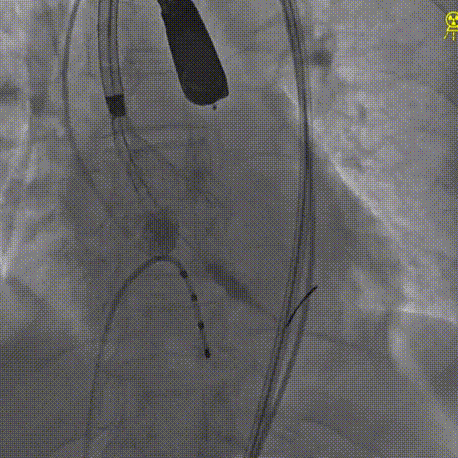

经左股动脉穿刺,置入6F股动脉穿刺鞘,将猪尾导管引导至主动脉根部,行主动脉造影。

术前主动脉造影